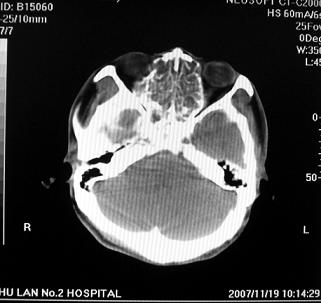

标题: CT10521:男。32岁,副鼻窦ct,请会诊。

男。32岁,鼻塞,流涕一年余。

软组织密度影填满上颌蚪 筛窦及鼻腔,并导致筛骨 上颌窦内侧壁明显骨质破坏。多考虑:内翻性乳头状瘤!

双侧鼻腔内低密度软组织影,骨壁无明显破坏,鼻腔无扩大,双侧上颌窦、筛窦软组织影,窦壁增厚,结合临床考虑鼻息肉合并慢性上颌窦炎。